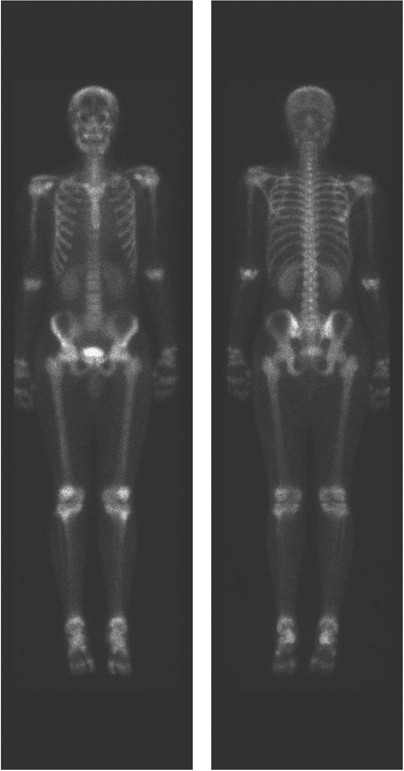

Calcineurin-inhibitor induced pain syndrome CIPS is a condition characterized by lower extremity pain in patients receiving tacrolimus or cyclosporine therapy following organ transplantation.

The most commonly implicated drugs are cyclosporine and tacrolimus. Calcineurininhibitoren sind Arzneistoffe mit immunsuppressiver Wirkung. 2 It has not yet been described in the literature with pimecrolimus. Through two cases we demonstrate key imaging findings in CIPS with bone scintigraphy and magnetic resonan. Calcineurin-inhibitor induced pain syndrome CIPS is a condition describing reversible lower extremity pain in patients following organ transplantation. Calcineurin-inhibitor induced pain syndrome after stem cell transplant.